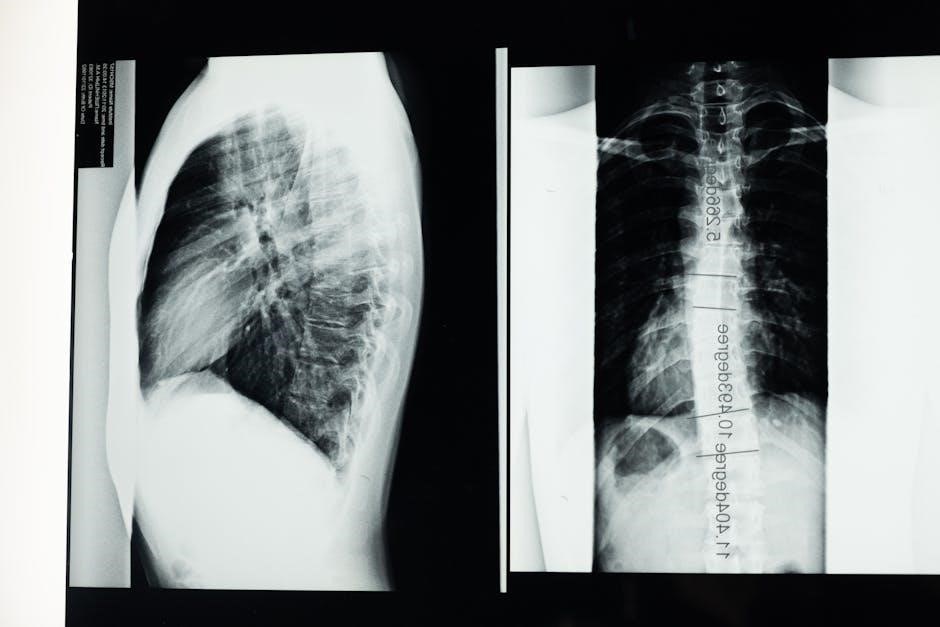

Lumbar spinal stenosis often presents with lower back pain, numbness, tingling, or weakness in the legs, especially when standing or walking. Symptoms may improve with rest or bending forward. Neurogenic claudication, a condition causing pain or cramping in the legs during activity, is common. Diagnosis typically involves MRI or CT scans to confirm spinal canal narrowing, along with physical exams and sometimes nerve studies. Early identification of symptoms is crucial for timely intervention, as untreated stenosis can worsen, impacting daily function and quality of life. Accurate diagnosis guides effective treatment plans, including exercise and lifestyle modifications.